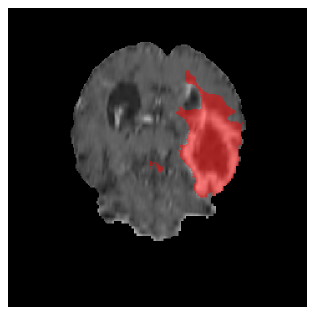

Figures 4 and 5 present the segmentation results for a patient from the BRATS dataset, visualized on a randomly selected slice. Figure 4 illustrates how tumor segmentation evolves over multiple episodes in S1 across different approaches including cumulative, naive, our approach, and the best buffer-free strategy (SI, =2). The cumulative approach, which trains on all encountered datasets together, maintains segmentation consistency across episodes but introduces significant amounts of false positives, particularly in the upper left area of the brain images. These misclassifications highlight its inability to generalize well across datasets despite access to all previous data. The naive approach, which learns sequentially without any continual learning strategy, suffers from severe catastrophic forgetting. While it initially segments well, performance deteriorates over episodes, leading to a near-complete loss of segmentation capability by the final episode. The SI (=2) approach, a regularization-based buffer-free CL strategy, performs reasonably well in early episodes but shows a significant performance decline over time. By the last episode, much of the tumor was no longer segmented, indicating difficulty in retaining prior knowledge. In contrast, our proposed approach initially produces more false positives but progressively refines its segmentation. By the final episode, it accurately retains the tumor region while minimizing misclassifications, demonstrating strong knowledge retention and adaptability across episodes. This suggests that our approach effectively mitigates catastrophic forgetting while maintaining segmentation performance over sequential learning.

Figure 5 illustrates the segmentation evolution for the same BRATS patient in S2 sequence. The key difference here is that the best buffer-free strategy is EWC (=1), and training on BRATS data starts from episode 2 instead of episode 1 as BRATS is encountered at episode 2 in S2. The cumulative approach retains segmentation across episodes but continues to generate false positives, which become even more pronounced in the final episode. The naive approach, lacking a CL mechanisms, completely overrides previous knowledge, leading to failed segmentation in later episodes. EWC (=1) approach initially maintains segmentation but experiences a sharp decline in episode 4, where it fails to segment the tumor. In the final episode, it undersegments the lesion, missing a significant portion of the tumor. In contrast, the proposed approach consistently preserves segmentation across episodes. While initially introducing false positives, it gradually refines predictions, retaining the tumor region while minimizing misclassifications. It maintains clear tumor delineation by the final episode, demonstrating effective knowledge retention and adaptability throughout training.